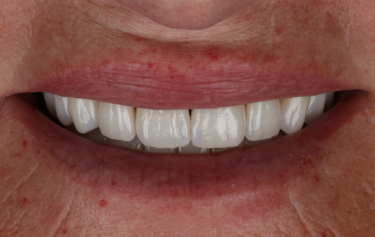

Figure 1: Full smile – before

Her main concern was the size discrepancies and tooth wear that was obvious within her smile. She had a low lip line and slightly deficient buccal corridors (Fig. 1). She was posturing into a pseudo-class 3 occlusion with passive overeruption of all her teeth, more noticeable on the anterior upper and lower labial segment (Fig. 2). She had missing posterior teeth and so all her mastication was on a reduced dental arch.

The patient returned after two weeks, and the final restorations were once again assessed. All margins, occlusion and excursions were re-checked and there were no further adjustments necessary (Fig. 24 & 25). Note the beautiful tooth morphology and the detailed surface texture that is achievable with modern digitally designed tooth libraries and state-of-the-art milling machines. The transfer of digital design to final restoration is an exact replication and this can be seen on the comparison of digital overlay against the final zirconia restorations in Figure 26

This patient’s smile is now better balanced, with whiter teeth and more symmetry to the shapes (Fig. 25). The final restorations will require twice yearly review to monitor and assess occlusal stability and function. Over time the posterior support will be re-addressed, and implants again considered.